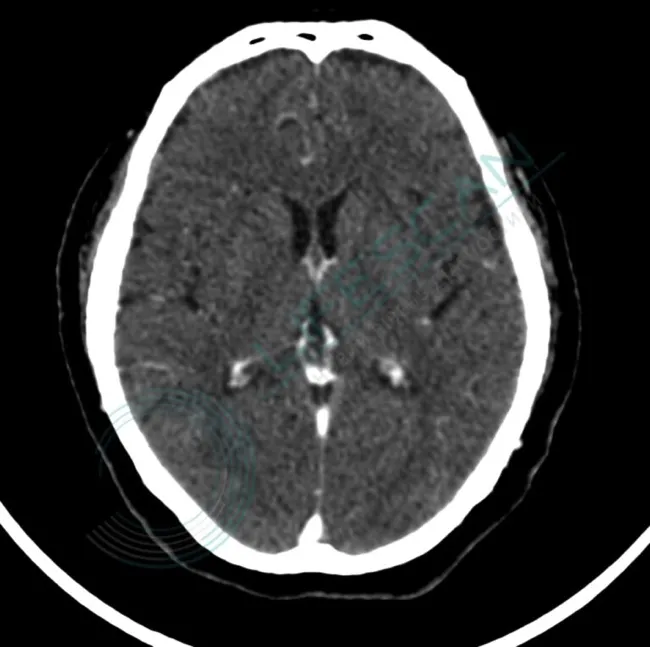

Якщо після цих обстежень виникне підозра на рак головного мозку, пацієнту буде проведене візуалізаційне обстеження. Зазвичай це магнітно-резонансна томографія (МРТ). Іноді можуть знадобитися додаткові процедури візуалізації, такі як:

- комп’ютерна томографія (КТ);